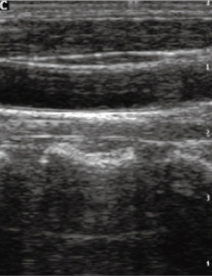

Технология SRA - подавляет шумы, оптимизирует контраст, снижает зернистость изображения, тем самым делает его более точным, что облегчает анализ (слева - без SRA, справа - режим SRA)..